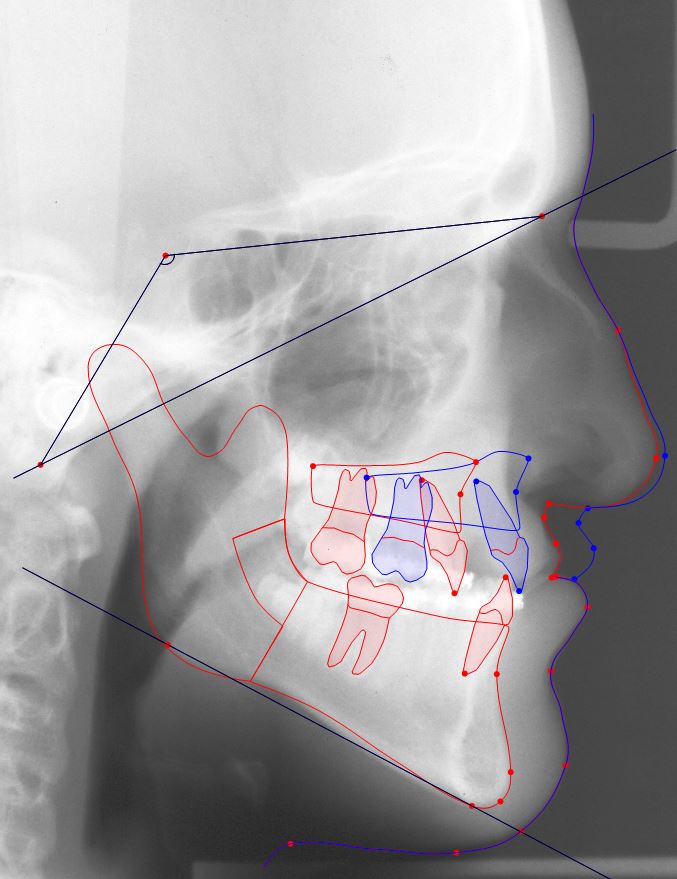

The orthodontic tracing software Facad has been in clinical use for more than 20 years.